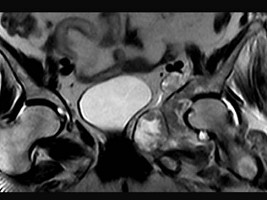

[单选题]患者,男,38岁,左髋部疼痛,并逐渐加重,体检:左髋部明显肿胀压痛,无明显发热,结合所提供的图片,最可能的诊断是()A .骨巨细胞瘤B .纤维肉瘤C .骨肉瘤D .软骨肉瘤E .软骨黏液纤维瘤

[单选题]患者,男,38岁,左髋部疼痛,并逐渐加重,体检:左髋部明显肿胀压痛,无明显发热,结合所提供的图片,最可能的诊断是()A . 骨巨细胞瘤B . 纤维肉瘤C . 骨肉瘤D . 软骨肉瘤E . 软骨黏液纤维瘤